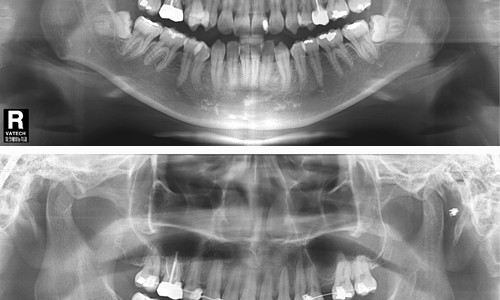

파크에비뉴치과 사랑니 발치 전 후 비교

위 두 환자는 교정치료를 위한 공간확보가 필요하여 사랑니 발치를 하게 되었다. 아래턱에 점선으로 표시 되어있는 하치조신경 다발이 사랑니 뿌리에 근접하여 지나가서 난이도가 높은 수술이었지만 3차원적 영상인 CT와 Panorama X-ray를 정밀 분석하여 발치 한 결과 신경 손상 없이 발치 할 수 있었다. 또한 두 환자 모두 “PRF(자가골성장인자)”를 이용해 사랑니 발치를 하여 부작용을 최소화 하였다.